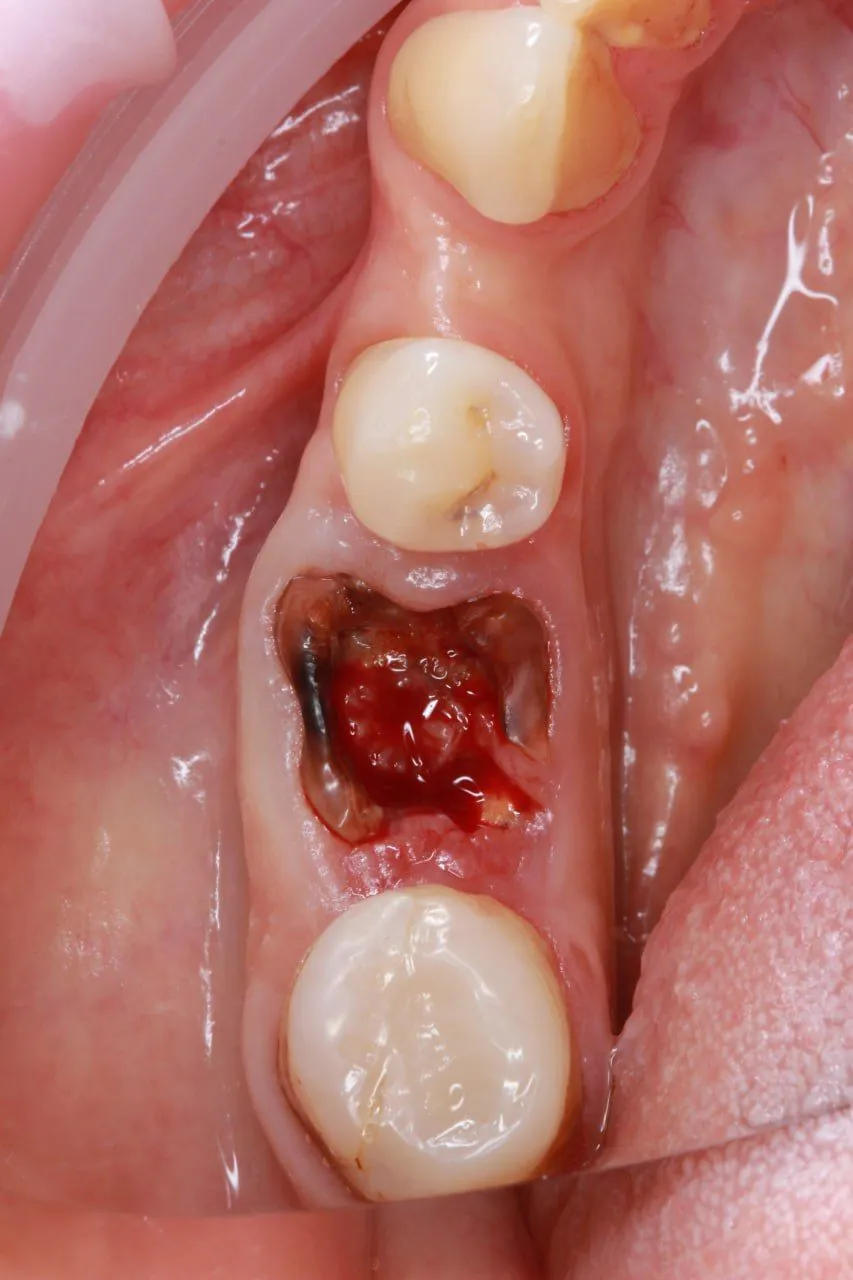

Пациент 52 года, обратился по поводу разрушенного зуба на нижней челюсти.

Проведено удаление зуба 36 и одномоментную установку импланта.